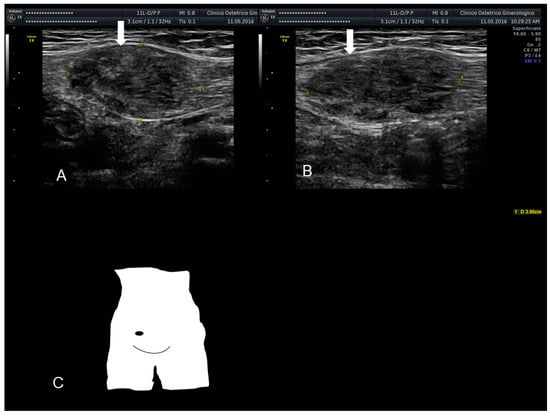

2.3. Umbilical Endometriosis or Villar’s Nodule

Villar’s nodule is characterized by the presence of endometrial tissue in the umbilicus as a result of tissue seeding during surgery (Figure 3, Figure 4 and Figure 5). It is a rare condition and it is iatrogenic in the vast majority of cases, correlated to previous abdominal/uterine surgery, although there have been very few reports of umbilical endometriosis without a history of previous pelvic surgery (Figure 3) [17].

This site of extra-genital endometriosis was reported for the first time by Villar in 1886 and since then about 100 cases have been described in the literature. It represents about 0.5–1% of all extra-pelvic locations of endometriosis [18]. Umbilical endometriosis usually appears in patients of reproductive age as a solitary lesion, in the absence of concomitant pelvic locations of disease, unlike other types of endometriosis [18]. From a morphological point of view it presents as a small bluish-pink mass, with a diameter ranging from a few millimeters up to 6 cm, a tendency to swell and cause painful symptoms, particularly in the premenstrual period, and possibly bleeding through the skin covering the umbilicus during menses, earning the title of “menstruating tumor”(Figure 3, Figure 4 and Figure 5).

This umbilical endometriosis may appear as solid areas with ill-defined margins (Figure 3, Figure 4 and Figure 5) that can be irregular or spiculated [11], but more frequently than other endometriotic lesions they may have a cystic appearance (although Nuck nodules may also have this appearance) [18] (Figure 3, Figure 4 and Figure 5). In fact, the typical US finding is a nodular formation that occupies the umbilical scar, with ground-glass echogenicity, irregular margins, and no papillary structures with a detectable blood flow [7]. The absence of continuity with the deep fascial plane allows its differential diagnosis from invasive malignancies and hernias [18].

Figure 3. The ultrasonographic appearance of a Villar’s nodule (see white arrows) in a woman without previous abdominal surgery.

Figure 4. The ultrasonographic appearance of a Villar’s nodule (see white arrows) using B-mode (A) and color Doppler (B,C) with some color spots due to peripheral vascularization in a woman without previous abdominal surgery. In this case the ultrasonographic appearance was more cystic than solid (AC). The nodule at visual evaluation (D).